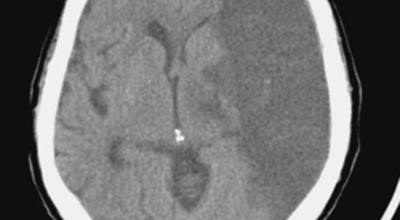

뇌경색 증상이 처음 나타난 후 4-5시간이 경과하지 않았다면 주사 제제를 통한 혈전용해술을 시도해 볼 수 있어요. 24시간이 경과하지 않았고 대뇌혈관이 막힌 것을 확인하였다면 막힌 혈관에 대하여 기계적 재개통술을 시도할 수 있어요.